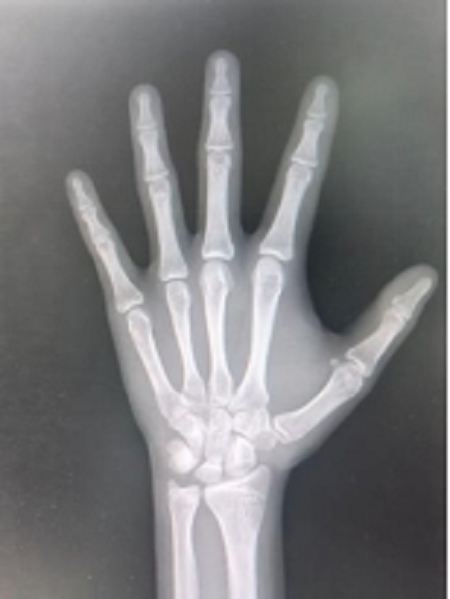

图片2

骨骺线尚未闭合状态